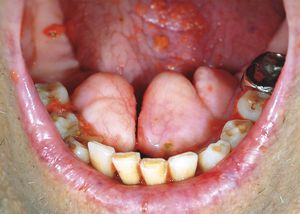

A 79-year-old man was admitted to the medical intensive care unit because of acute respiratory failure, cardiogenic shock, acute kidney injury, and urinary tract infection. He had a long-standing history of cor pulmonale. Incidentally, he was noted to have abnormalities on the lingual surface of the lower jaw. Three bony outgrowths were seen and diagnosed as mandibular tori (also known as tori mandibulares). The patient reported no history of a chewing disability, dysphagia, dysarthria, oral ulcers, or sleep disturbances associated with the oral findings. The patient recovered from cardiogenic shock and was discharged home. Tori are benign exostoses, and in most cases, the finding is incidental and requires no intervention, as in this case. Possible reasons for extirpation would be the need for prosthetic treatment and the need for a potential source of grafts, as in periodontal surgery. Sridhar Badireddi, M.D. University of Arkansas for Medical Sciences, Little Rock, AR Neeraja J. Boddu, M.D. Central Arkansas Veterans Healthcare System, Little Rock, AR source: nejm.org